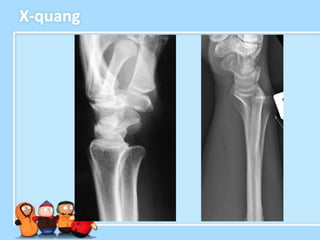

X-quang